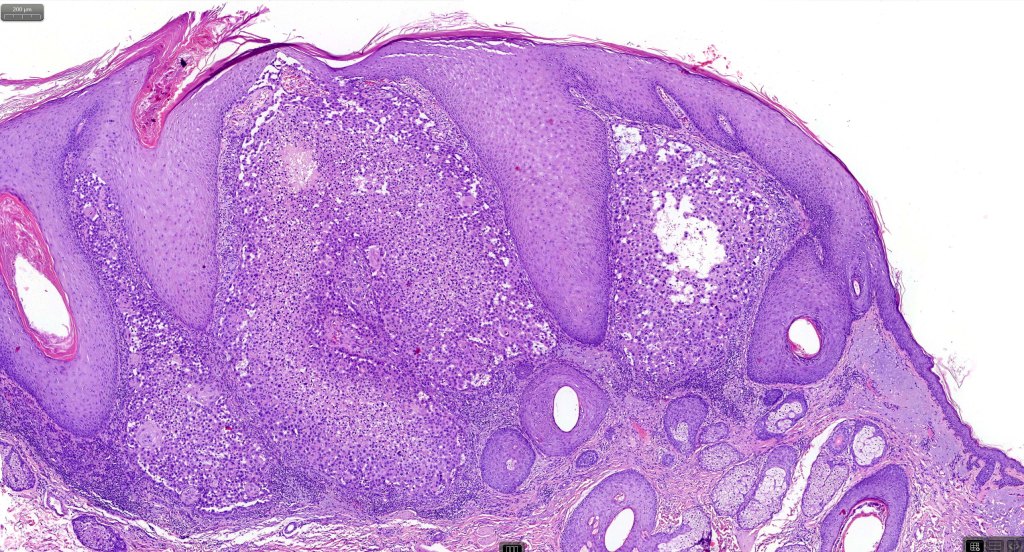

Histological features

•Acantholysis gives rise to a pseudoglandular appearance

•Often well differentiated

•May be folliculocentric rather than arise from the epidermis